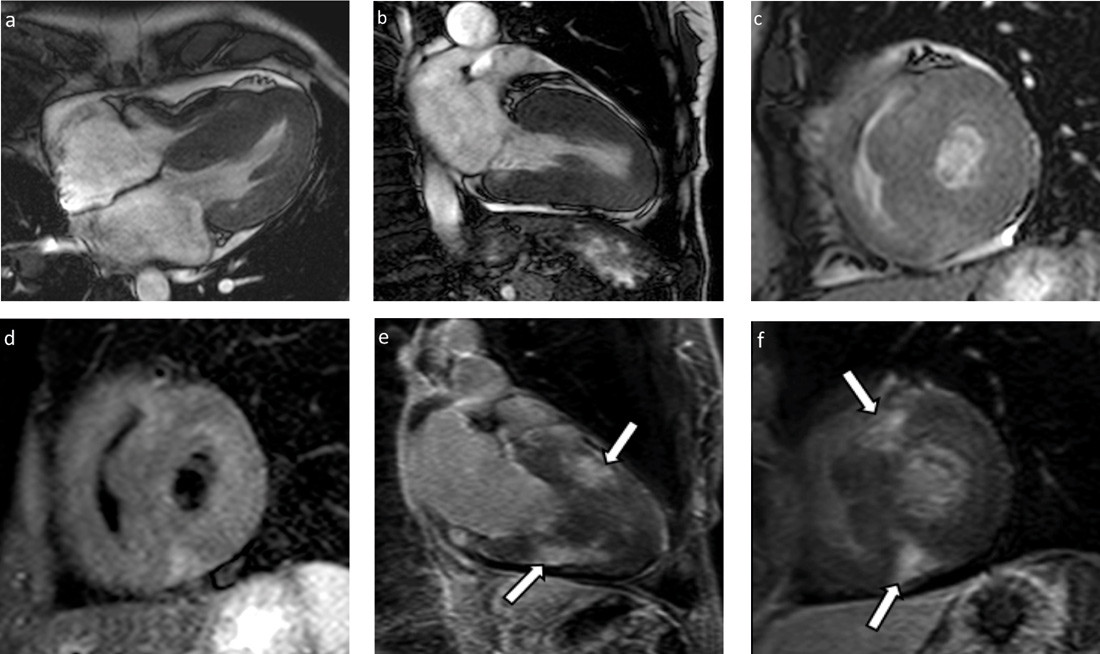

MR-undersøkelsen ble gjennomført med funksjonsserier i tre plan, T2-vektet kortakse før og T1-vektet serie i kort- og langakse etter intravenøs gadoliniumkontrast (fig 3). Undersøkelsen bekreftet ujevn myokardfortykkelse i begge ventrikler, spesielt fremtredende i septum. Begge atrier var lett forstørret, og det ble påvist lettgradige mitral- og trikuspidalinsuffisienser, uten hemodynamisk betydning. Ejeksjonsfraksjonen ble estimert til 65 % (> 60 %), og venstre ventrikkels myokardmasse ble beregnet til 135 g (70 – 180 g). Det ble påvist flekkevise, store områder med kontrastoppladning (late gadolinium enhancement, LGE), mest uttalt anteroseptalt og inferiørt i venstre ventrikkels myokard. Områder med kontrastoppladning var lokalisert sentralt i myokard eller transmuralt, men ikke subendokardialt. I tillegg ble det funnet noe perikardvæske samt flere forstørrede glandler, særlig i høyre hilusregion.

MR-undersøkelsen bekreftet diagnosen restriktiv kardiomyopati og styrket mistanken om avleiringssykdom i myokard. Med bakgrunn i de kardiale funn ble endomyokardial biopsi diskutert, men det vurdert som lite hensiktsmessig, da forandringene var ujevnt lokalisert. Muligheten for å treffe et patologisk område ble ansett som liten. Dessuten hadde pasienten uttalte forandringer i lungehilus. Biopsimaterialet fra dette området var så langt ikke representativt for konklusiv diagnostikk.